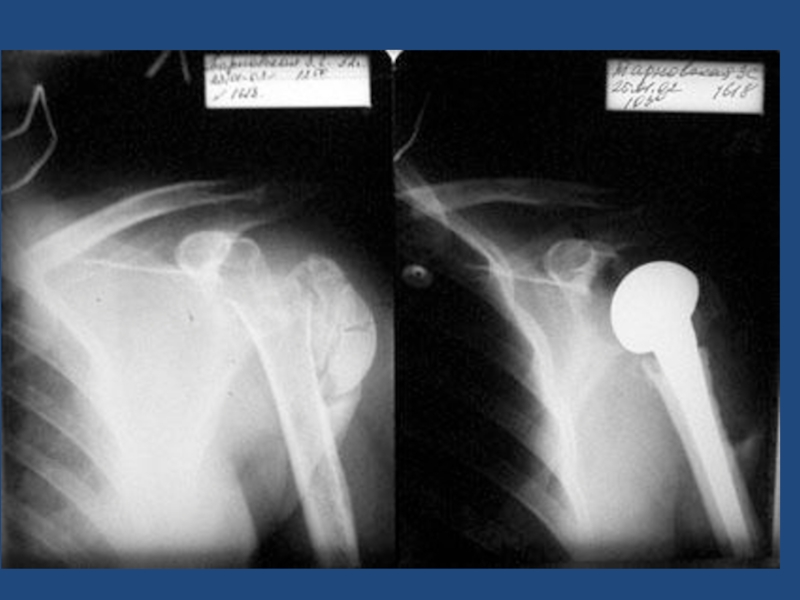

Слайд 2221

Передне-нижний вывих плеча подклювовидный?

Полный вывих акромиального конца ключицы